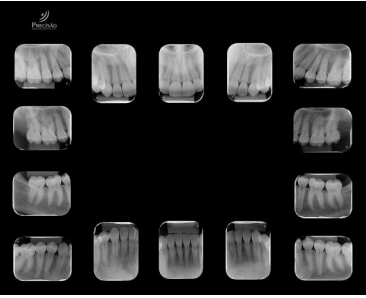

Analise os exames radiográficos a seguir:

De acordo com as imagens acima, é correto classificar essas radiografias como: